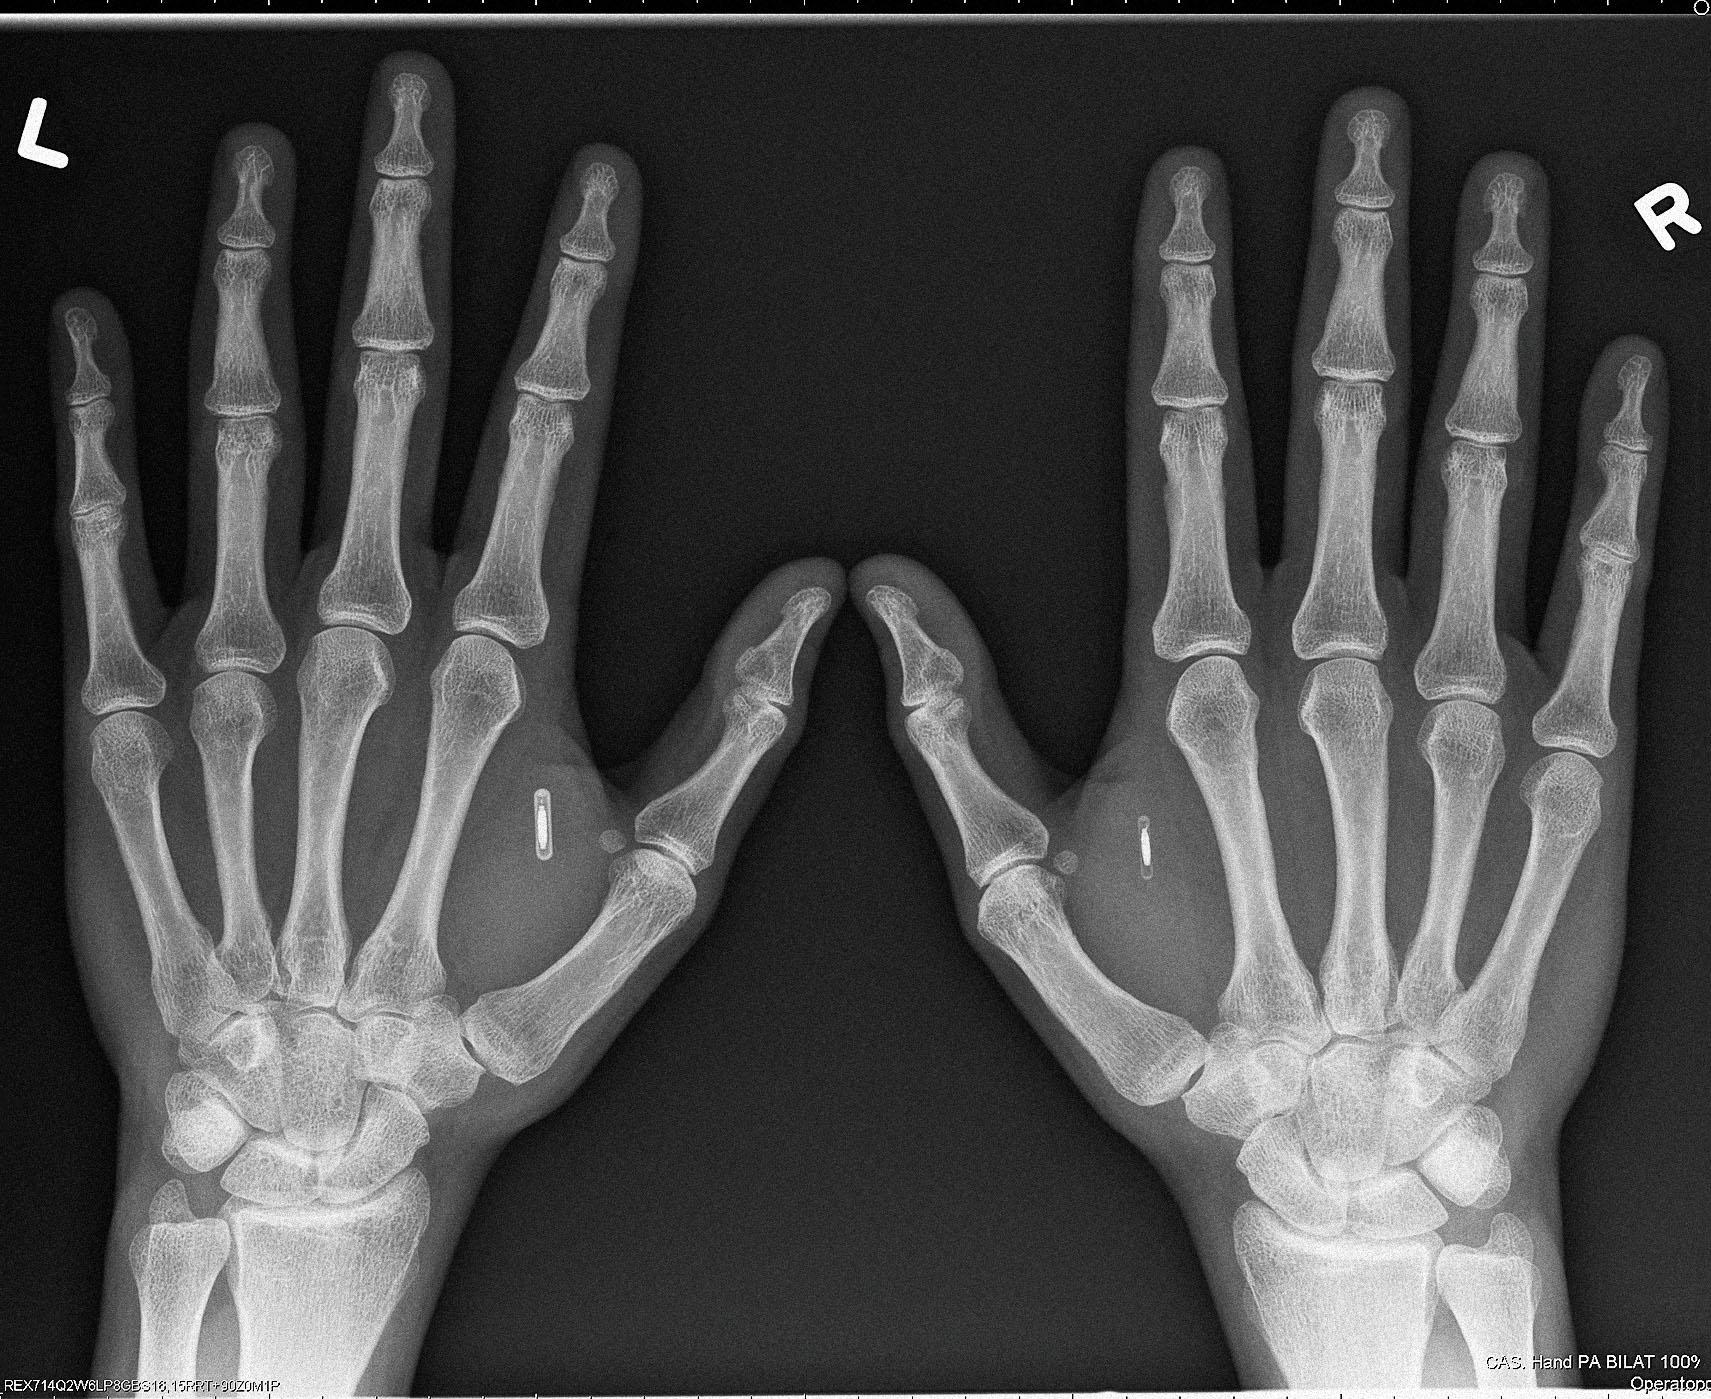

Бывший IT-консультант из Сиэтла Амаль Граафстра носит под кожей четыре NFC- и RFID-чипа собственной разработки и продает тысячи таких же девайсов «киборгам»энтузиастам по всему миру, в том числе в России. Журнал РБК узнал у основателя компании Dangerous Things, как устроен бизнес по «роботизации» людей и зачем его клиенты вживляют в себя «умные» импланты

Все началось в 2005 году. «Я тогда работал в IT-консалтинге медицинских учреждений, часто засиживался в офисе допоздна и при этом постоянно забывал ключи. Чтобы не запирать себя, придумал такую альтернативу — вживить под кожу чип». Технологию операции он почерпнул у ветеринаров, которые чипируют домашних животных при помощи специальной иглы. Чипы для питомцев Граафстре не подошли: девайсы производятся из материалов, которые человеческий организм может отторгнуть. Граафстра решил собрать чип самостоятельно. Детали, не вызывающие аллергии, он заказал в интернете, а первый чип собрал дома. Он остановился на технологии беспроводной передачи данных NFC, сегодня встроенной в большинство смартфонов: «Я сразу понял, что за ней — будущее. NFC-чипы тогда еще никто массово не производил и уж тем более не вживлял в себя».

Цена на чипы разнится в зависимости от серии. Серия X — самые популярные из-за простоты установки NFC- и RFID-транспондеры. Их Dangerous Things продает по $79, они не требуют подзарядки и способны нести информацию о пользователе, его электронные ключи. Следующая серия — Flex. Это чип в гибком биополимере стоимостью $200. Если девайсы серии X можно вживить только под кожу между большим и указательным пальцем «ветеринарной» иглой с чуть увеличенным диаметром, то Flex размещаются чуть выше запястья, а их «установка» требует небольшой хирургической операции.

Срок годности чипов, по словам Граафстры, до 30 лет. В интернет-магазине Dangerous Things продаются также необходимые для проведения операции (иглы, скальпели, обезболивающие и т.д.) и программирования микрочипов инструменты (ридеры, стикеры и т. д.). Граафстра постоянно разрабатывает новые устройства, с которыми взаимодействуют импланты, например «умное» ружье, стреляющее только в руках владельца. В последнее время предприниматель работает над проектом VivoKey. Это вживленное в руку зашифрованное хранилище данных. «Главная цель устройства — переместить ключи шифрования данных туда, где их не смогут достать злоумышленники», — рассказывает Амаль.